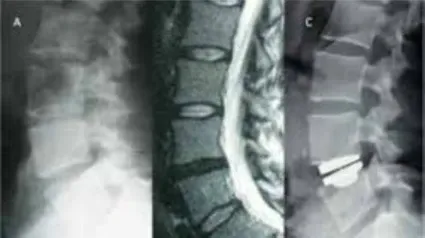

Este tipo de prótesis se pone en personas más jóvenes